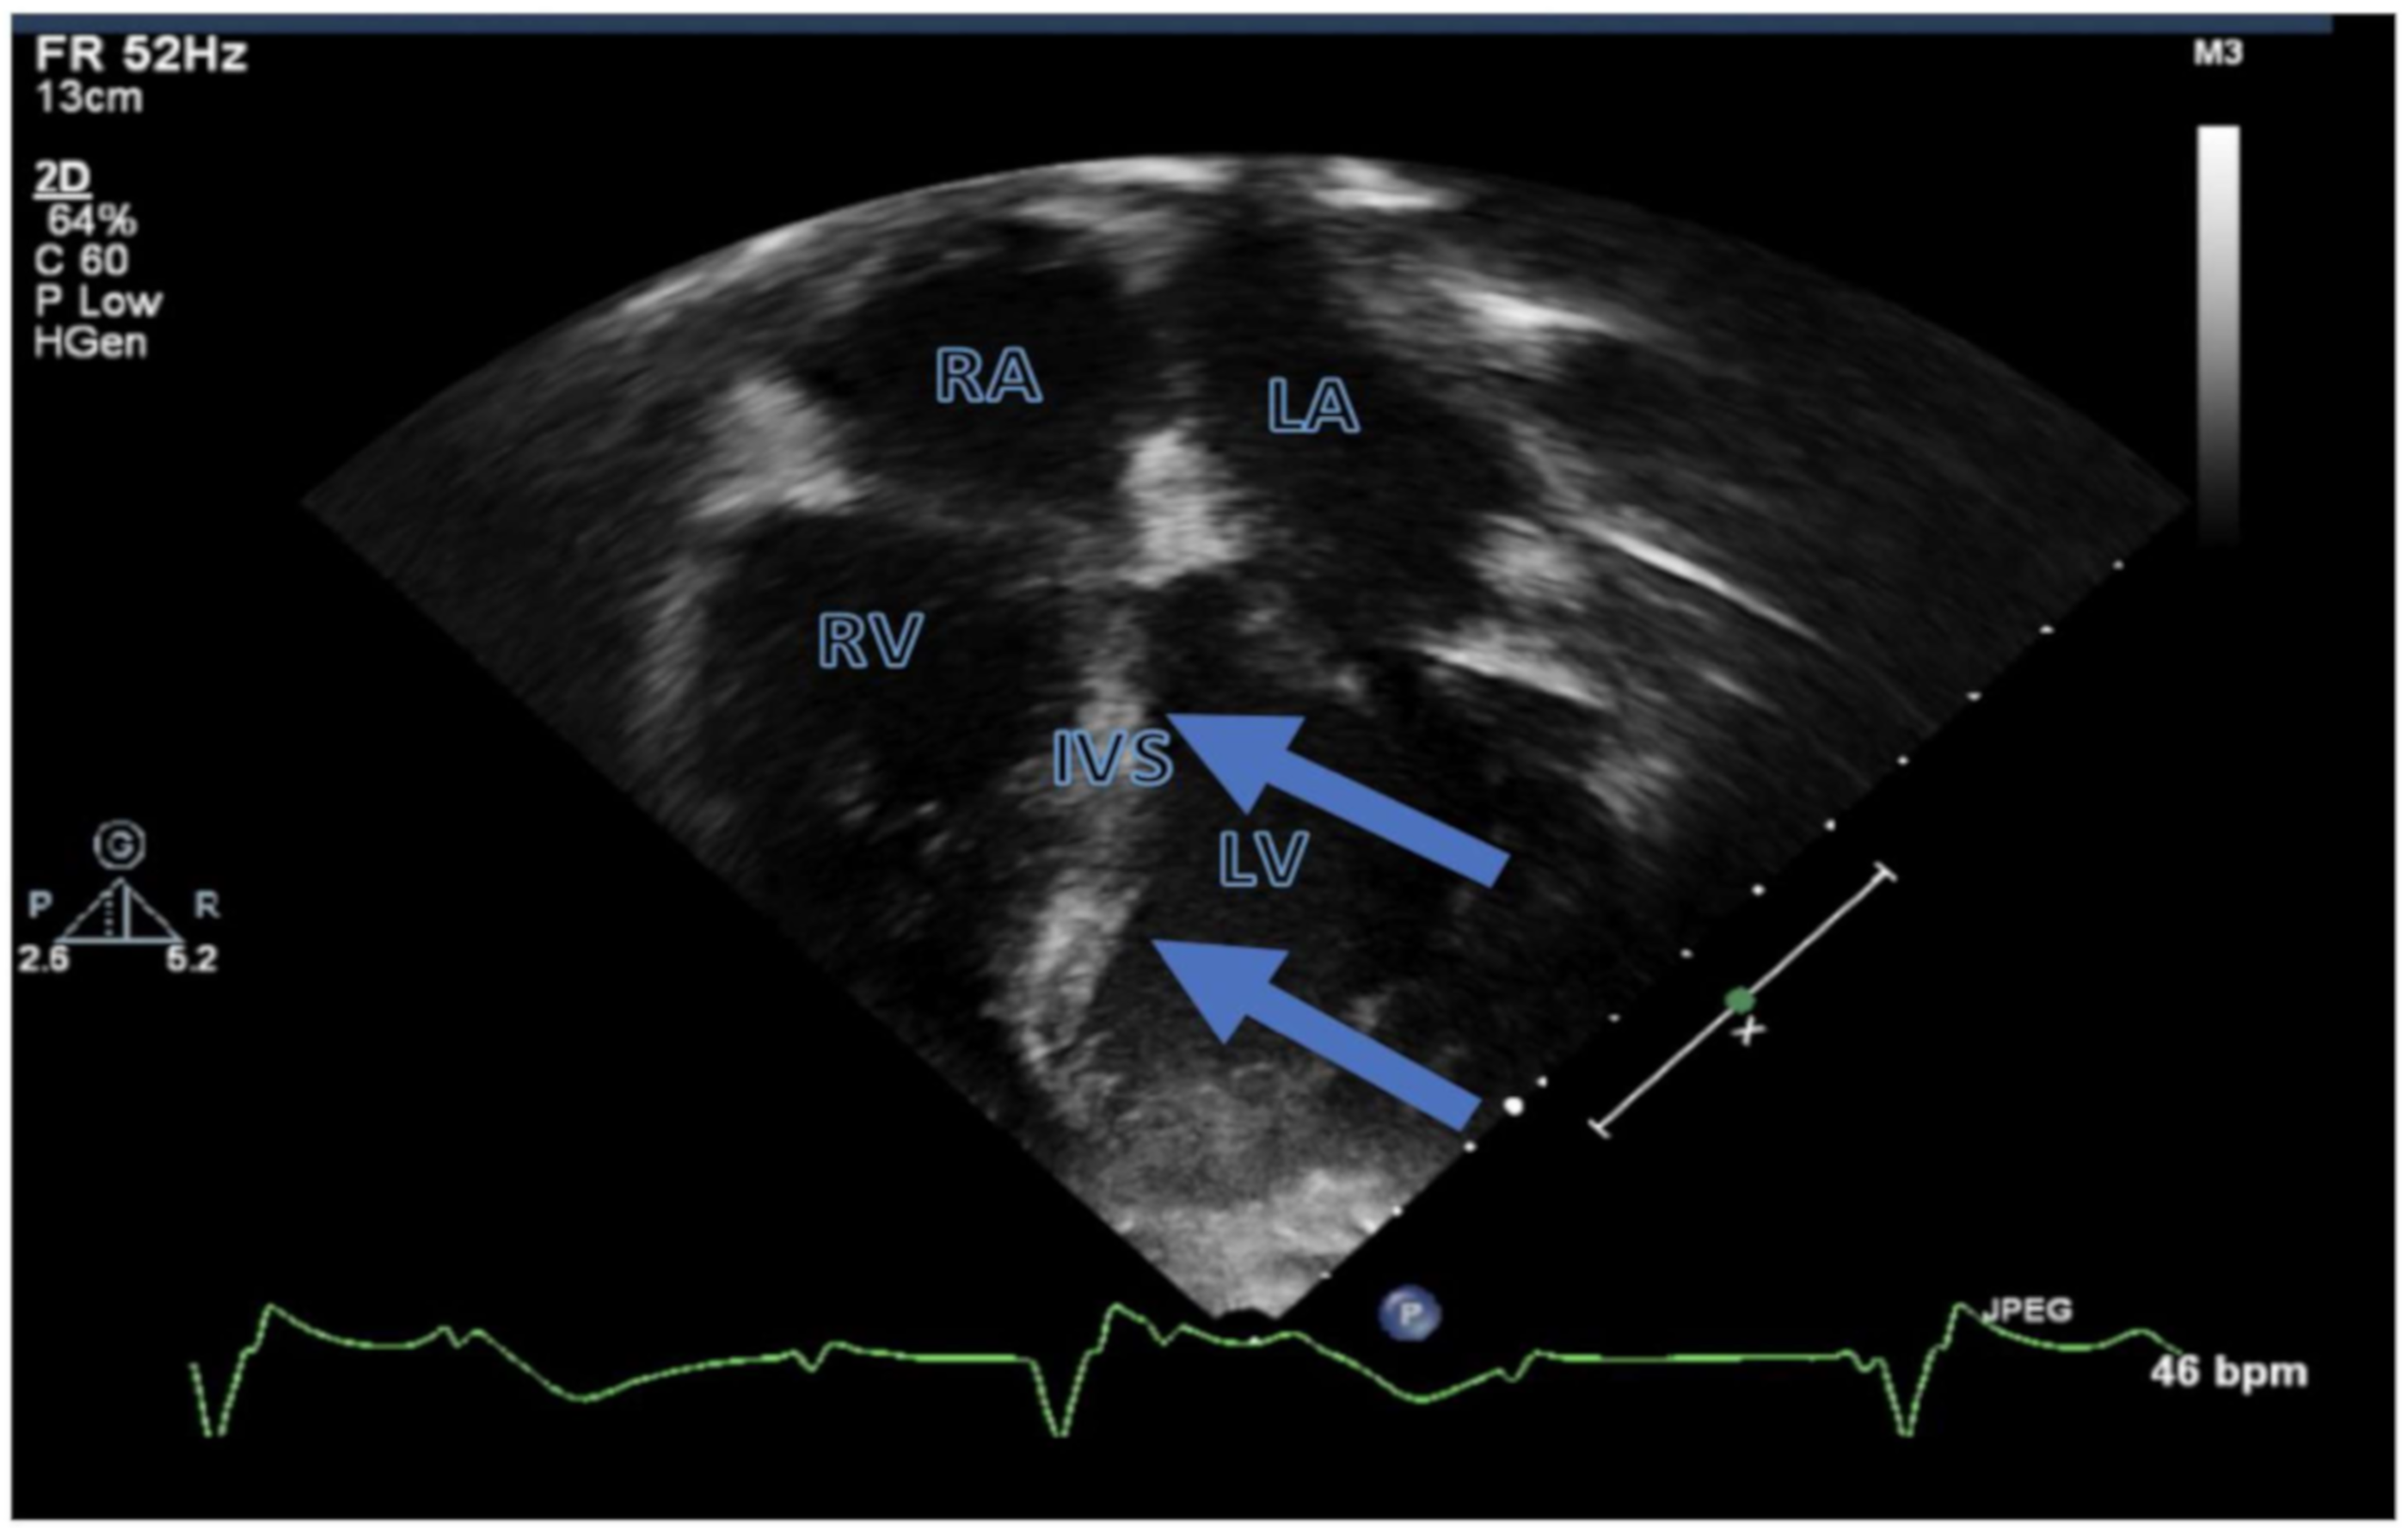

| Symptomatic cardiac relapse |

| Death due to severe LV systolic dysfunction and loss of AV conduction |

| Hori et al. (2006); Malbora et al. (2010); and Barbaric et al. (2002) [2,11,12] | Systemic leukemia involving the heart | Adolescents presenting with cardiac symptoms related to leukemic involvement of the heart; echocardiogram and chest imaging may help with diagnosing leukemic involvement of the heart |

| Wiernik et al. (1976); Hardikar et al. (2002); Espino et al. (2001) [16,17,18] | Systemic leukemia involving the heart | Signs and symptoms of cardiac involvement of leukemia: respiratory symptoms, pleural or pericardial effusions, and cardiomyopathy; require distinguishing from treatment related adverse effects |